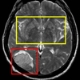

• Innovative Therapien bei Schlaganfall: Interregionale Tagung in Bozen

Interregionale Tagung zu Schlaganfällen in Bozen

LPA - Experten aus Tirol, Trient und Südtirol befassen sich am 28. Juni in Bozen bei der Tagung „Iktus“ mit neuesten Erkenntnissen zur Vorbeugung, Diagnose und Therapie bei Schlaganfall. Die Tagung wird vom Landesamt für Krankenhäuser in der Landesabteilung Gesundheitswesen organisiert und vom EVTZ „Europaregion Tirol-Südtirol-Trentino“ unterstützt.